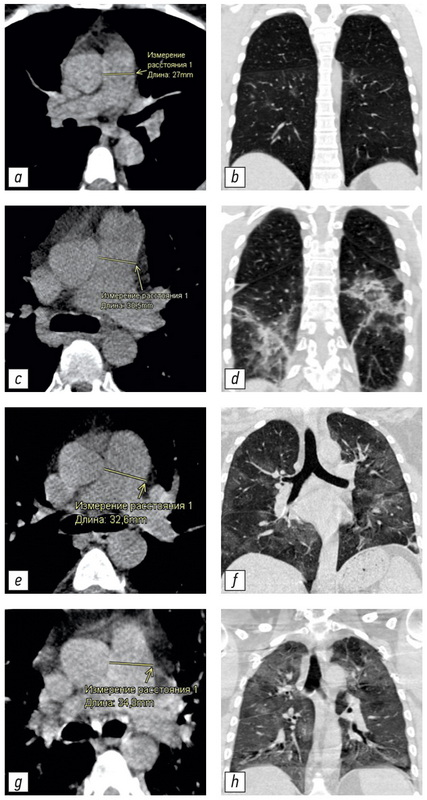

材料与方法患者组中进行单核单级固体不受控制的研究 (n=511,267男性,中美洲59岁,IQR 49.0-65.0,范围从31至84岁),在临时医院治疗COVID-19患者。 随着住院治疗,所有患者都通过了使用IISRO Truct Mobile System(Stryker,美国)的胸部器官的计算机断层研究。 CT 1-4规模上估计了轻微组织的病变程度。 通过垂直于容器的长轴的放射科医生的工作站的标准工具来进行光动脉直径和上升主动脉的测量。

结果。获得以下统计学显着的模式:光动脉的膨胀和光动脉/升序姿势的升高与COVID-19肺部病变程度的增加有关(克拉克尔-沃利斯准则,p <0.001;中值测试,p <0.001); 升高主动脉的直径随着患者的年龄而显着增加(克拉克尔-沃利斯准则,p <0.001;中值测试,p <0.001)。 显示了光动脉直径和患者年龄的直径之间的不准确的关系(克拉克尔-沃利斯准则,p=0.094;嗜源性测试,p=0.311)和腹腔直径的变化和肺部的病变程度之间的不准确的联系(克拉克尔-沃利斯准则,p=0,061;中值测试,p=0.165)。 所有年龄段的疾病方面和大量的肺病灶(KT-3和KT-4)中,可靠地增加了患有轻质高血压症状的患者(从29毫米和更多的光动脉膨胀)是显示。

结论。光动脉的扩张和光动脉/升序的直径比率的增加与在所有年龄组中COVID-19的肺病变的体积增加是可靠的